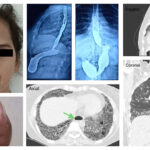

Exposure to air pollution, such as high levels of particulate matter from fire smoke and fossil fuel-related nitrogen oxides, may increase the risk of rheumatoid arthritis (RA) and RA-associated interstitial lung disease (ILD), according to Kronzer et al. Their findings highlight the need for improved monitoring of air pollutants and suggest that addressing air pollution may help prevent RA and RA-associated ILD.